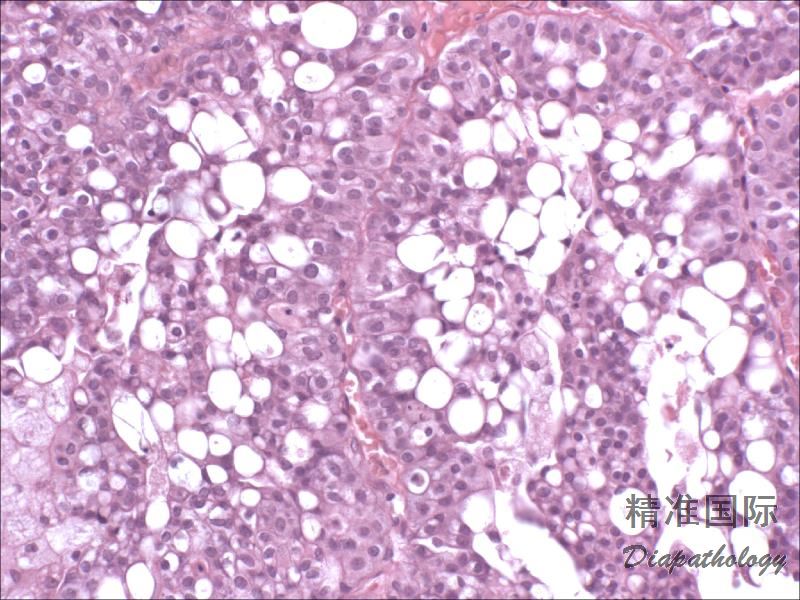

浸润性尿路上皮癌,富脂质

Infiltrating urothelial carcinoma, Lipid-rich

尿路上皮癌瘤细胞胞浆内存在多个空泡挤压核形成类似于脂肪母细胞的瘤细胞

特征性形态学改变是存在大的脂肪母细胞样细胞,具有 1 个或多个胞浆空泡,挤压细胞核;

常和其它类型或普通型尿路上皮癌混合存在,脂质细胞通常占肿瘤成分的 10%-50%,